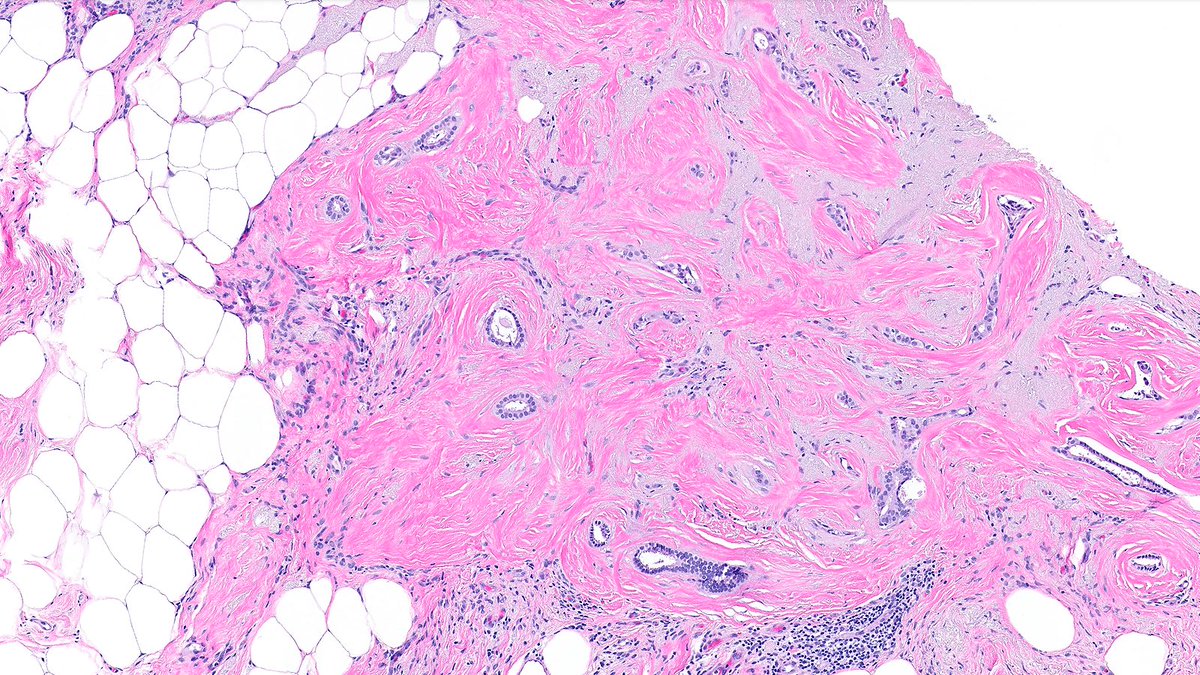

Case of Radial Scar 🗿🔬

Central fibroelastic core with entrapped glands radiating outward 🌟.

A master of masquerade, fibroelastotic nidus can simulate desmoplastic stroma—p63 shown below 👇.

#PathX #PathTwitter #breastpath